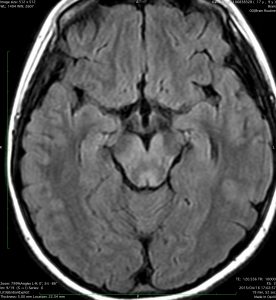

MRI画像診断

- MRIでは脳幹部(とくに橋)が腫れて大きくなります

- 多くの場合は左右対称ですが,非対称のものもめずらしくありません

- MRIのFLAIR(フレア)画像とかT2強調画像で,白くぼーっと滲んだように映ります

- 脳幹部の橋というところを中心にして発生し,上方の中脳や下方の延髄に浸潤して伸びていきます

- 腫瘍は大きいのですが,水頭症にならないのが特徴です(水頭症は2割くらい)

- 上の写真の例では,症状は軽く,たいていの場合はこのくらいの大きさになってから発見されます

- 腫瘍の前方の中心に黒い点のようなものが見えますが,これは脳底動脈で,この脳底動脈の囲い込み engulfment は,DIPGに特徴的なものといえます

- 腫瘍の一部分だけが脳幹部から突出してキノコのように伸びる所見 exophytic grwoth は2割くらいにみられます

- 腫瘍内部に小さな腫瘍内出血が生じることもあります